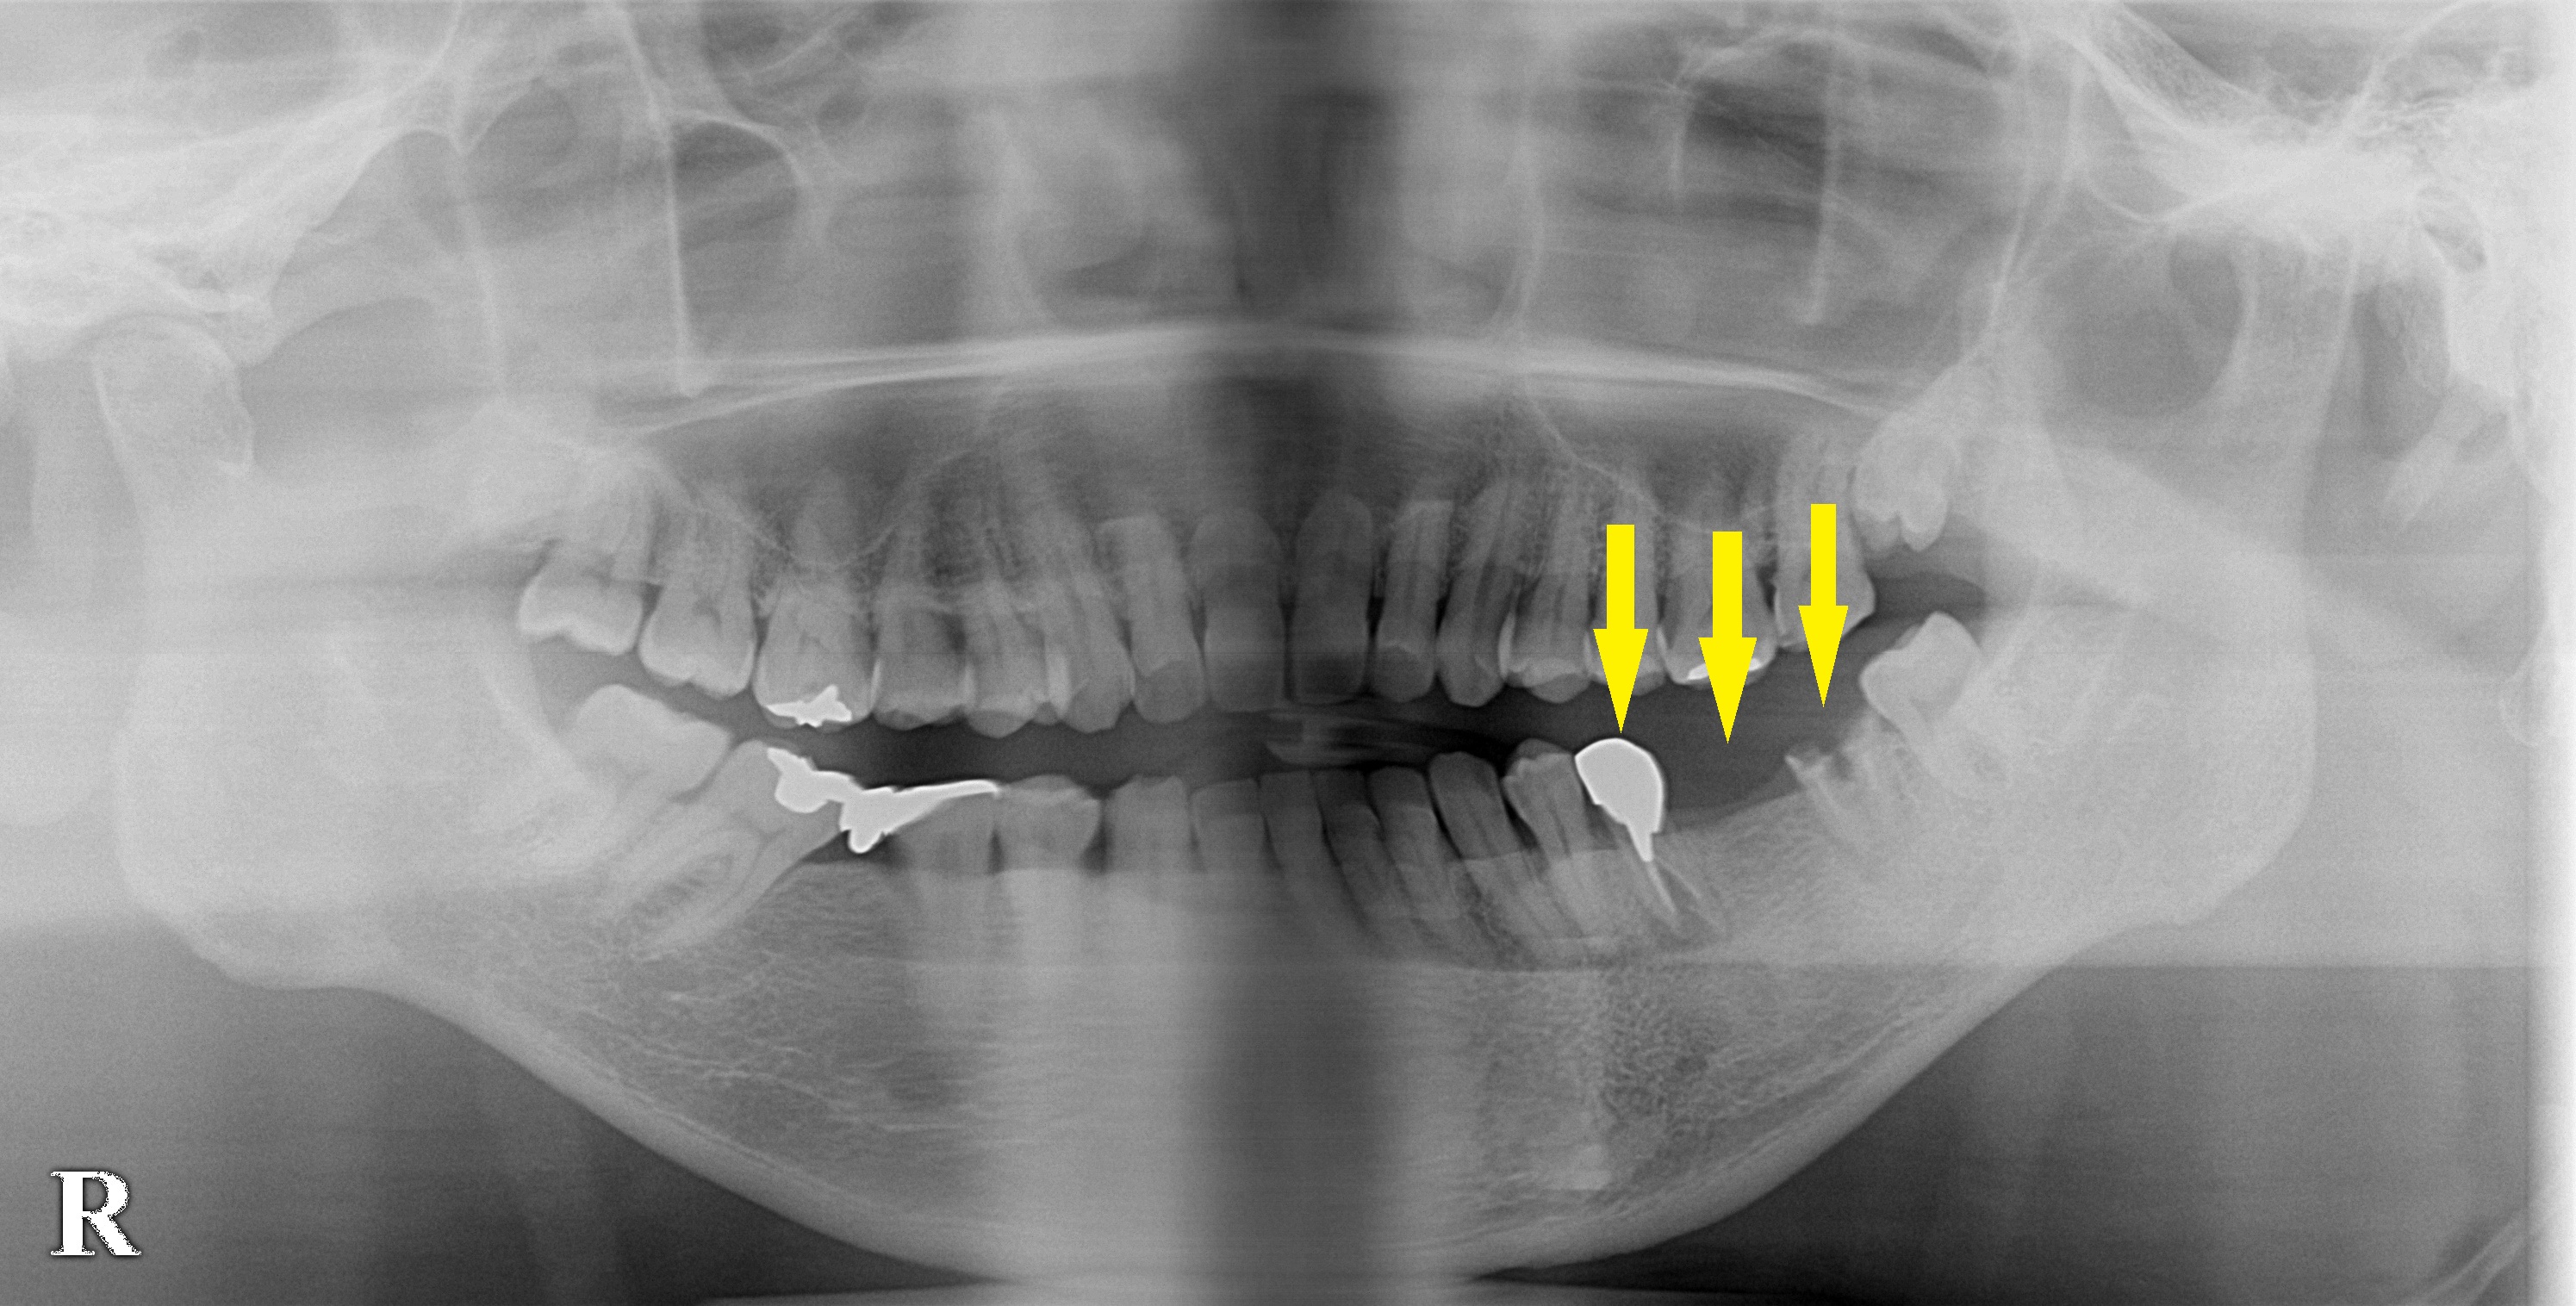

左下顎臼歯が破折してしまい、抜歯して、インプラントか義歯かと言われたそうです。

破折した歯の周りの骨が吸収されてしまっているので、抜歯即時埋入ではなくて、抜歯してから、十分治癒を待っての埋入手術としました。

咬む力も非常に強そうですので、3歯の欠損に対し、3本のインプラント埋入を行うこととし、本日埋入手術を行いました。